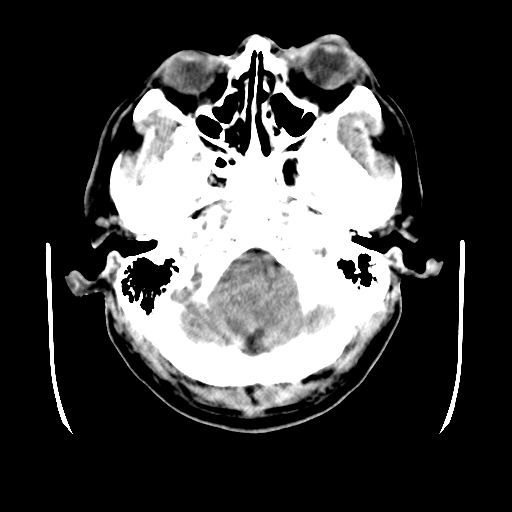

男,51岁,头外伤一小时,呕吐两次。

蛛网膜下腔出血 脑肿胀

左侧颞部硬膜外;蛛网膜下腔出血 ;脑肿胀

1)左侧中颅窝蝶骨翼后方硬膜外血肿。2)左侧颞顶部硬膜下血肿。3)蛛网膜下腔出血。4)左侧筛窦及双侧蝶窦炎症(或积血)。5)左侧额部头皮软组织肿胀。

蛛网膜下腔出血

左侧硬膜外 下血肿  硬膜下血肿影不出外是蛛网膜下腔出血

左颞顶不头皮血肿,左侧颞不硬膜(下)血肿,蛛网膜下腔出血

1:左侧硬膜外及硬膜下混合血肿。2:蛛网膜下腔出血。3:左额部少量颅内积气?

左颞部硬膜外血肿,蛛网膜下腔出血,副鼻窦积液.头皮损伤.